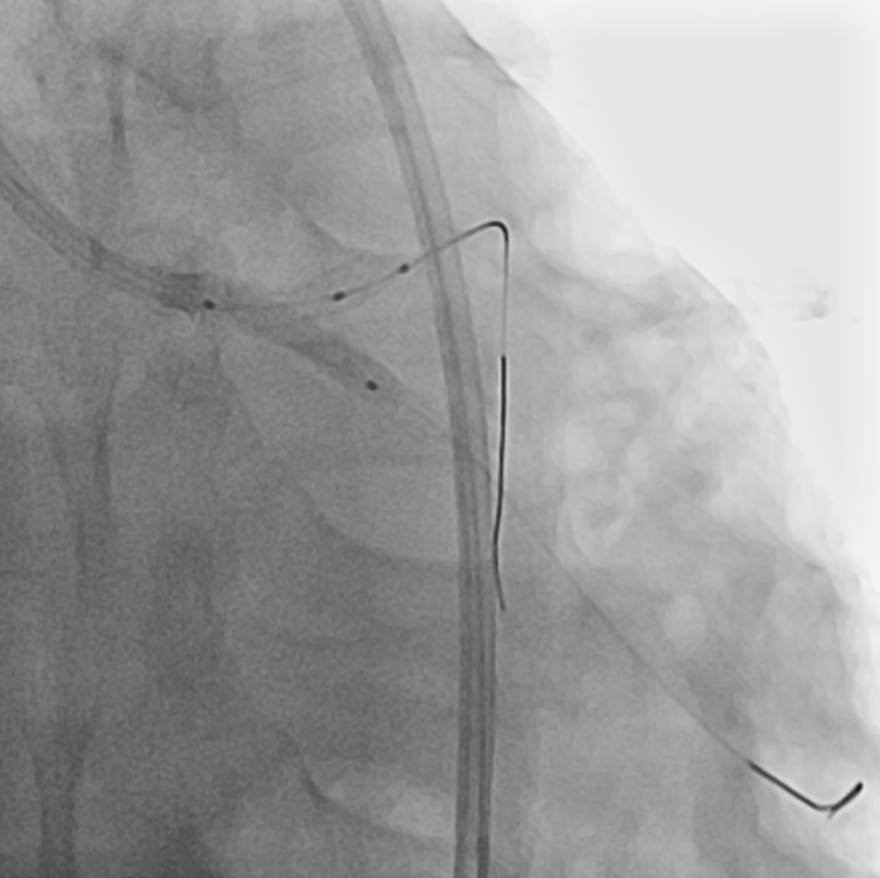

Coronary angiography revealed no specific findings in the right coronary artery, while showing collateral flow from the posterior descending artery to septal branches. Severe in-stent restenosis (ISR) was observed in the previous LM stent, accompanied by severe stenosis at the left circumflex (LCX) ostium resulting in TIMI flow grade 1.The procedure was performed via femoral approach using an 8 Fr sheath and Judkins 3.5 guiding catheter. Runthrough NS 0.014 wire was used for LAD wiring, which was successfully achieved. However, LCX wiring proved challenging and required a double lumen catheter (Asahi Sasuke 0.014, 3.2 Fr) for successful passage.Predilatation was performed using a semi-compliant balloon (Ryurei 2.0 ¡¿ 15 mm) for LCX and a non-compliant balloon (Selethru NC 3.5 ¡¿ 8 mm) for LM to LAD. Intravascular ultrasound (IVUS) evaluation was performed in both vessels to assess lesion characteristics. The treatment strategy involved drug-eluting balloon (DEB) therapy for LM-pLAD ISR and drug-eluting stent (DES) implantation in LCX with reverse crush technique.Additional lesion preparation was performed using a cutting balloon (Wolverine 3.5 ¡¿ 10 mm) for the LM-pLAD ISR lesion. A Xience 3.0 ¡¿ 15 mm stent was implanted in the proximal LCX. The LCX stent was then crushed using a non-compliant balloon (Selethru NC 3.5 ¡¿ 8 mm), followed by rewiring of LCX using the double lumen catheter and Fielder FC 0.014 wire.Kissing balloon dilatation was performed with non-compliant balloons (Selethru NC 3.5 ¡¿ 8 mm for LAD and 3.25 ¡¿ 15 mm for LCX) at 6 atm. Subsequently, drug-eluting balloon therapy (SeQuent Please Neo 3.5 ¡¿ 20 mm) was applied to the LM-pLAD ISR lesion, followed by final kissing balloon dilatation at 8 atm.Final IVUS evaluation confirmed optimal results in both LAD and LCX vessels. The procedure was completed without complications, demonstrating successful treatment of complex left main bifurcation disease with combined DEB and reverse crush stenting technique.